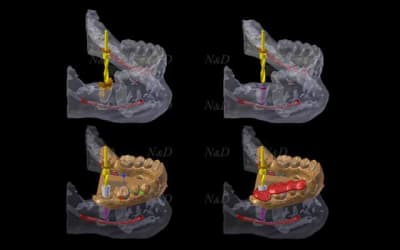

> voila comme promis une vidéo planif et guide entièrement faite avec blender sans utiliser meshlab

> Planif

> Collage du platre

> Guide

> Test des différents forets

un petit test avec mon nouveau jouet

1) plâtre cône beam dans invesalius

2) cone beam vs cam3d

3) collage dans blender

4) résultat